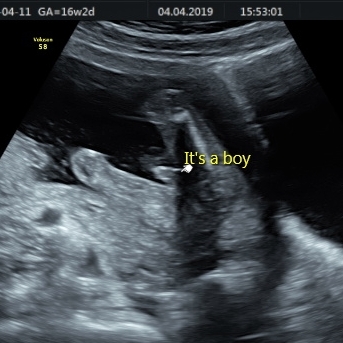

TwittleBee · 04/04/2019 20:56

Baby looks all good kyles101 and we are very very clearly having a boy!

kyles101 · 04/04/2019 21:11

Ha ha, no doubt about that one twittle congratulations 🥰